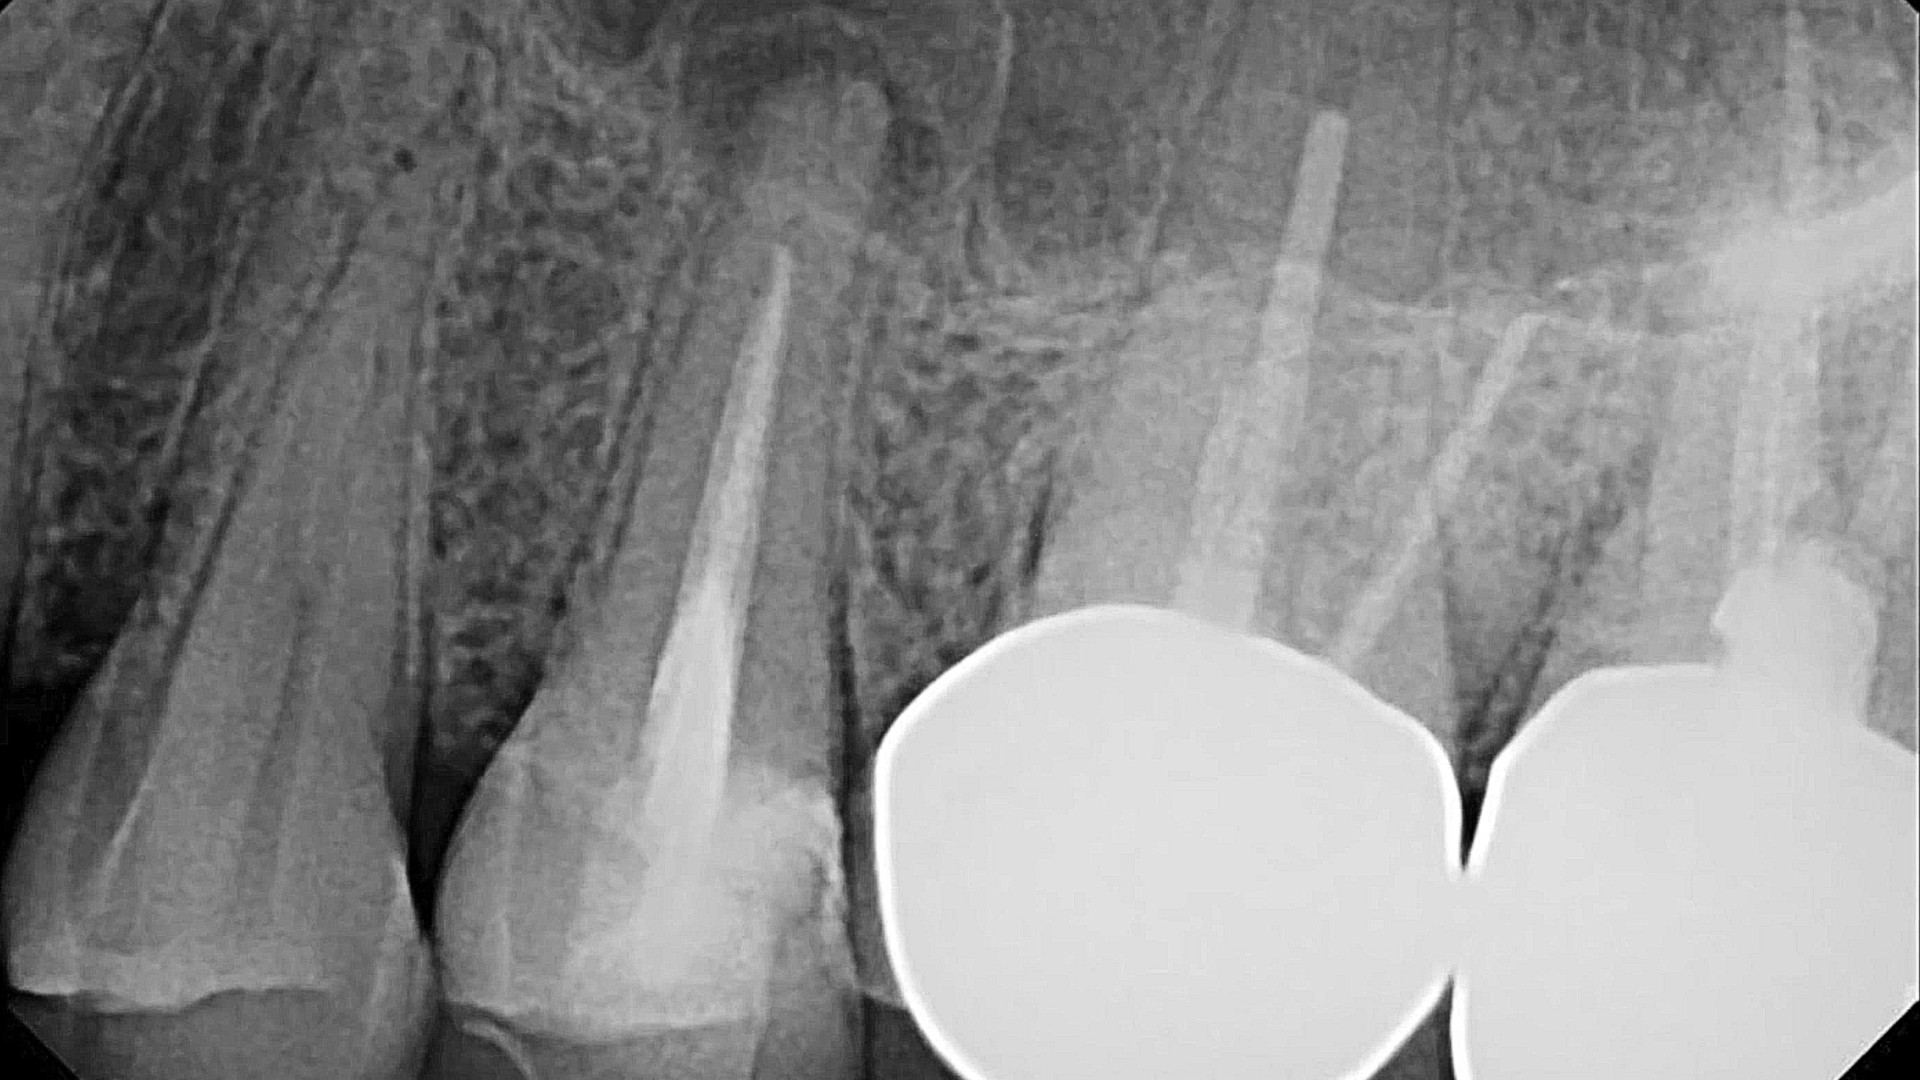

HOW TO MANAGE LARGE PERIAPICAL LESION WITH NON-SURGICAL ENDODONTIC TREATMENT